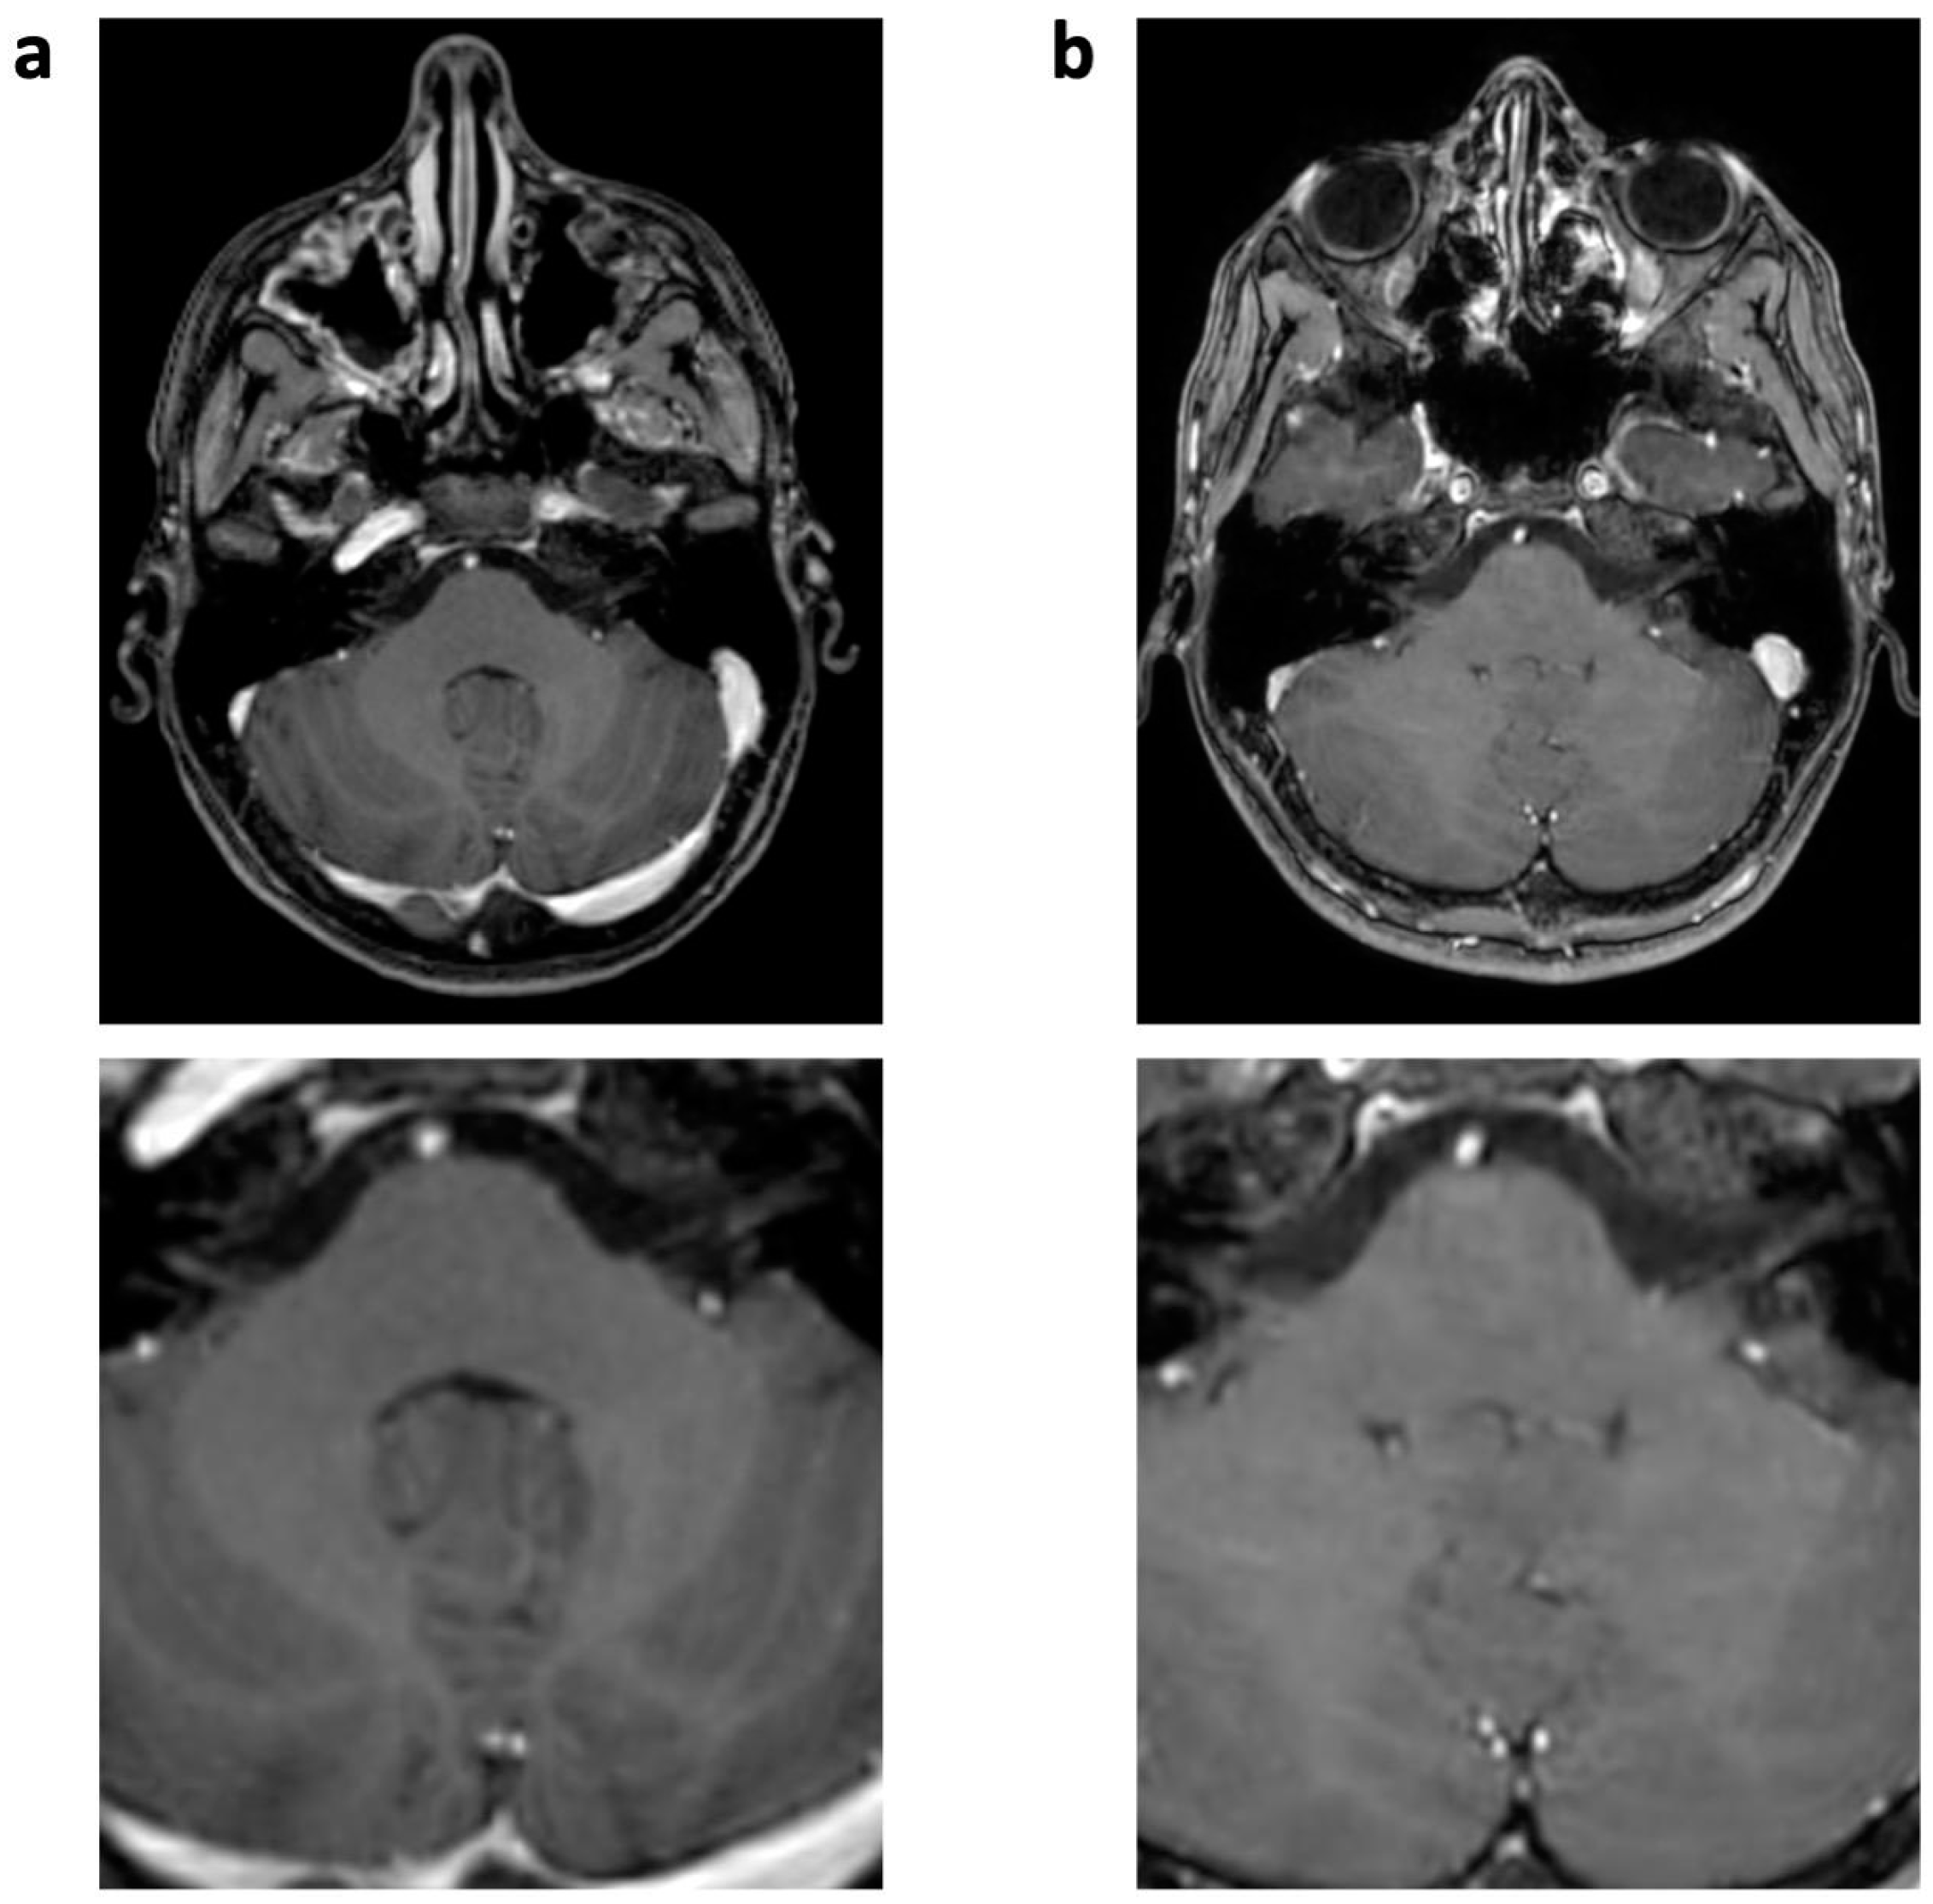

| Physiology-related | Motion | 10 (45%) | 11 (0.50 ± 0.60) | 0 | 0 | 0.005 |

| Ringing | 21 (95%) | 24 (1.09 ± 0.43) | 6 (27%) | 6 (0.27 ± 0.46) | <0.001 | |

| CSF flow | 22 (100%) | 43 (1.95 ± 0.21) | 8 (36%) | 8 (0.36 ± 0.49) | <0.001 | |

| Pulsation/ghosting | 18 (82%) | 30 (1.36 ± 0.79) | 0 | 0 | <0.001 | |

| Physics-related | Chemical shift | 6 (27%) | (0.27 ± 0.46) | 0 | 0 | 0.028 |

| Overall | 6.09 ± 1.72 | 1.68 ± 0.72 * | <0.001 | |||